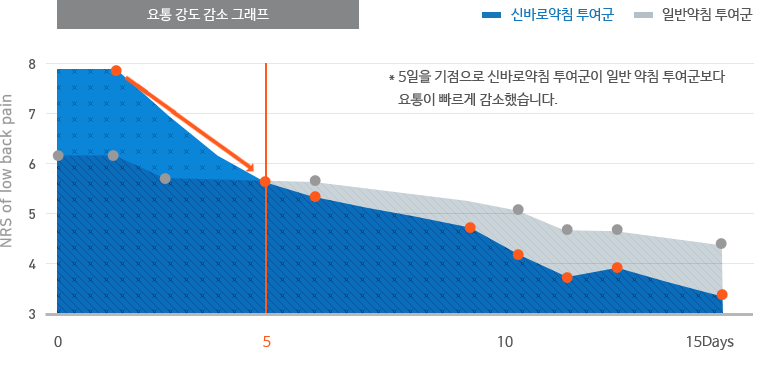

일반 약침보다 빠른 통증 감소 효과

자생척추관절연구소에서 디스크 환자를 대상으로 신바로약침과 일반약침의 효능을 비교한 임상연구 결과, 신바로약침

이 일반약침보다 척추디스크로 인한 허리통증과 다리통증을 더 빠르게 감소시키는 것으로 나타났습니다.

이 일반약침보다 척추디스크로 인한 허리통증과 다리통증을 더 빠르게 감소시키는 것으로 나타났습니다.

- 연구기관 : 자생한방병원

- 저널명 : 척추신경추나의학회지 2011;6(2):109-119

- 논문명 : 요추추간판탈출증에 대한 신바로약침의 효과 : 무작위 대조군 시험